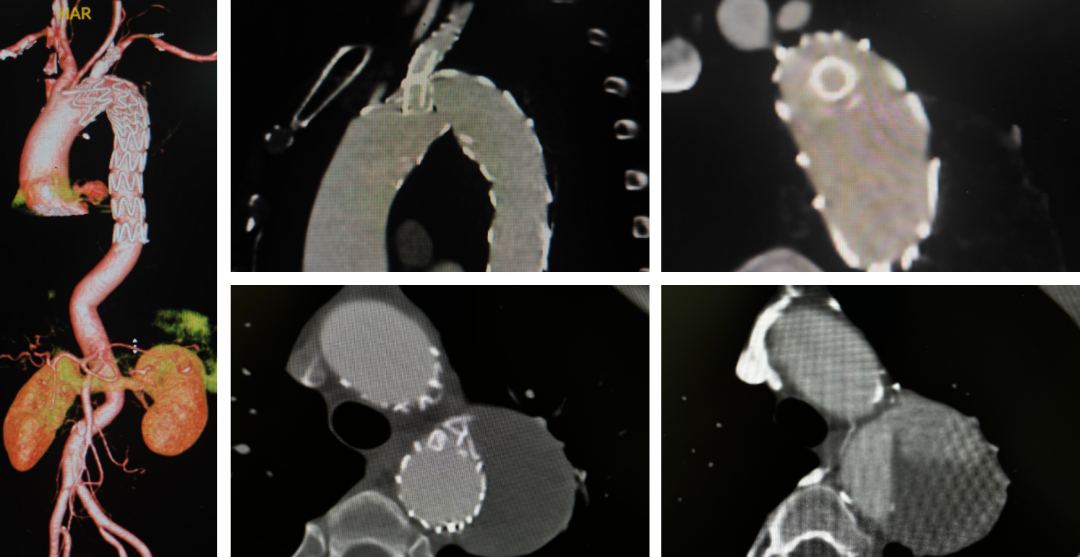

病例一(单开窗)

张XX,男,56岁,主动脉夹层。LSA单开窗。

术后